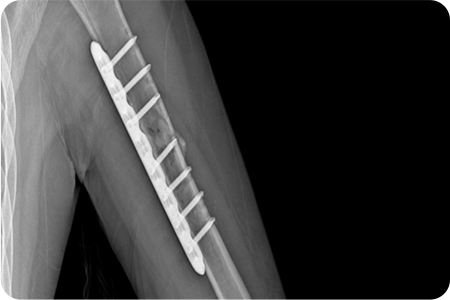

X-ray 및 CT를 통해 골절 형태와 전위 정도를 확인합니다.

골절된 뼈를 원래 위치로 맞추는 정복 작업을 진행합니다.

금속판, 나사, 고정막을 이용해 뼈를 고정합니다.

골절·외상 수술은 손상된 뼈와 조직을 정밀하게 맞추고 금속판·나사·핀 등을 이용해 안정적으로 고정하는 치료입니다.

이 과정에서 뼈의 정렬과 관절 기능을 회복하기 위한 섬세한 판단이 필요하기 때문에,